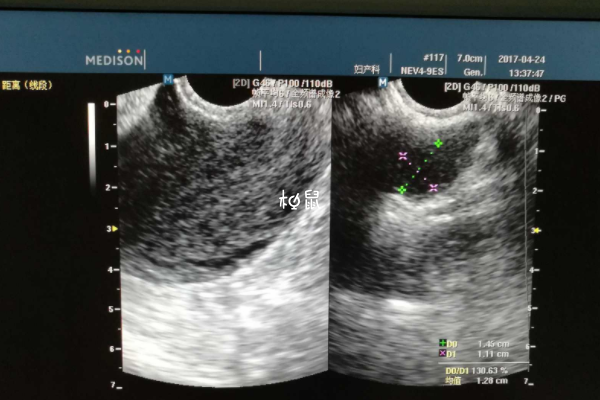

卵泡监测主要是看卵泡的发育过程以及是否有排卵,通过观察报告单上写的体内卵泡数量,以及卵泡的大小,可以判断出是否排卵,当报告单上卵泡数量减少,或者是成熟的大卵泡消失,只剩下未成熟的卵泡,就说明已经排卵了。

监测卵泡报告想要看卵泡多大了,可以观察报告单上的数字,比如说报告单上提示18*18mm,就说明有一个卵泡已经长到18mm了,此时卵泡已经发育成熟,有排卵的可能性,回去后安排同房即可。

通过报告单上的数字就能了解到卵泡发育情况,有的也会在数字后面对卵泡发育情况做一个解读,如果不知道卵泡发育多大,可以询问医生,在检查后医生也会分析结果,有不懂得也可以问。